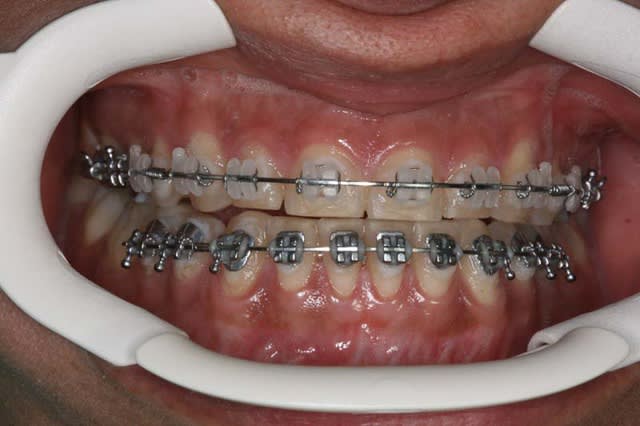

traité en technique de Burstone, puis en friction faible

Il s’agit d’un cas en transfert, qui n’est pas satisfaite du résultat de son traitement O.D.F. (Burstone)

Elle a consulté un chirurgien maxillo qui lui propose un chirurgie haut et bas, et lui a dit qu’elle aurait besoin d’une finition O.D.F.

Comme elle me parle d’extractions des PM. Inf., je lui demande les coordonnées de son chirurgien, et lui demande s’il ne préfère pas que je réaligne les Inc. Inf. avant la chirurgie, quitte à la mettre provisoirement en inversé d’articulé Ant.

Il et elle me donnent leur accord, voici les photos de départ

je la traite par les techniques de friction faible, et voici le résultat 1 an après

je ne suis pas en inversé d’articulé Ant. comme je pensais me retrouver !!!

et son profil s’est bien modifié